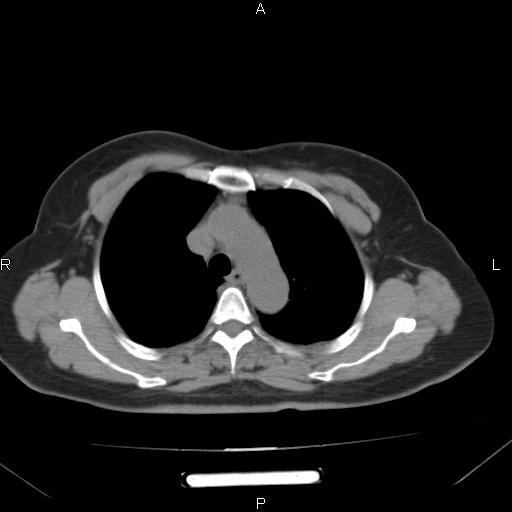

胸腺瘤

女、63Y 双眼睑下垂,早轻晚重。 胸腺瘤???

结果胸腺瘤